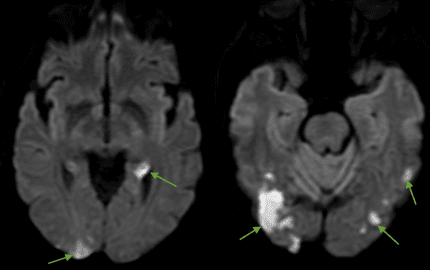

On hospital day two, he developed acute delirium, digital ischemia [Image 2], and right upper extremity pain. Brain MRI revealed multiple acute infarcts in bilateral frontoparietal, thalamic, and parieto-occipital territories [Image 3]. Despite therapeutic anticoagulation, a right upper extremity venous duplex showed acute brachial vein thrombosis. Anticoagulation was temporarily held, and warfarin was initiated due to suspected apixaban failure.

Laboratory workup revealed markedly elevated antiphospholipid antibodies (cardiolipin IgG >112 GPL, β2-glycoprotein I >112 SGU) and progressive thrombocytopenia (253K --> 91). Additional findings included retinal cotton wool spots and digital ischemia, confirming multi-organ involvement consistent with CAPS.